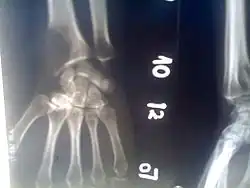

Osteolytic lesion

Osteolytic lesion at the bottom of the radius, diagnosed by a darker section that indicates a loss of bone density